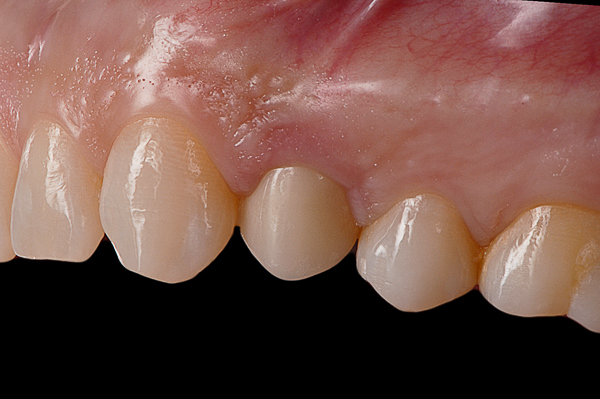

Il caso presenta la riabilitazione di un premolare superiore interessato dal fallimento di un trattamento endodontico in una paziente donna di 37 anni, non fumatrice e con una buona igiene.

A seguito dell'analisi radiografica viene pianificata l'estrazione atraumatica del premolare con l'inserimento contestuale di un impianto Shelta. La riabilitazione immediata viene eseguita con un pilastro XA per protesi avvitata, su cui viene fissato un provvisorio realizzato in laboratorio secondo i principi dei profili di emergenza della tecnica B.O.P.T.

Donna, 37 anni, non fumatrice, con una buona igiene, si presenta in studio con un fallimento del trattamento endodontico dell'elemento 1.4.